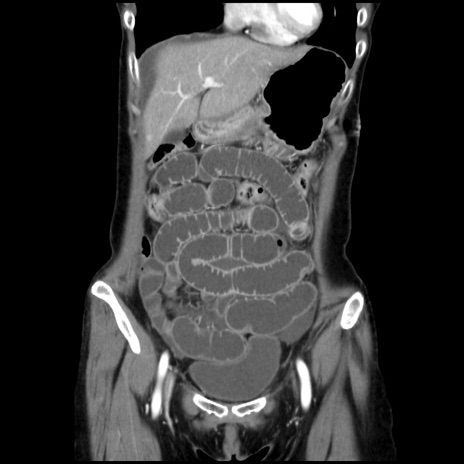

症例32(冠状断像)

【症例】40歳代 女性

【主訴】上腹部痛、嘔気・嘔吐

【現病歴】約9時間前頃から急に上腹部痛、嘔気、嘔吐が出現。改善しないため救急要請。

【既往歴】子宮頚癌(広汎子宮全摘術、放射線療法)、腸閉塞

【身体所見】腹部:平坦、軟、腸雑音亢進、上腹部を中心に腹部全体に圧痛あり。

【データ】WBC 8400、CRP 0.03